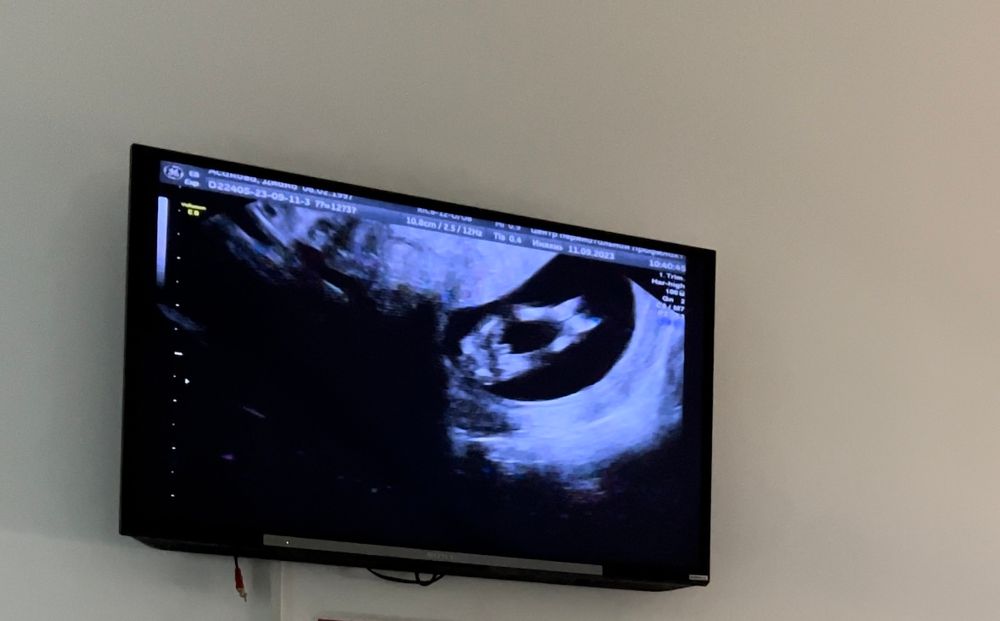

1 скрининг, пол ребёнка и маленький носик

Было подобное фото в 13 недель, но у нас было подлинне, и всё-таки оказался мальчик), поэтому даже не жнаю

По половом бугорку вроде девочка

В 12 недель прекрасно виден пол.Яички развиваются по другому,яичники по другому,не говоря уже про все остальное☺️сейчас не 20 век чтобы ошибаться,тем более мне кажется в Казахстане очень не плохие УЗИ аппараты стоят

Nani, дело де не только в аппаратах, но и в компетенции УЗИ врача. В совокупности таких факторов до сих пор очень много ошибок до 16 недель в определении пола. Только кровь даёт 99% результат. Даже в нашем веке

Я думаю это девочка.

У меня будет сын)) Половой бугорок )на 12 неделе мне на узи сказали мальчик ..но я не поверила так как тут бугорок пока